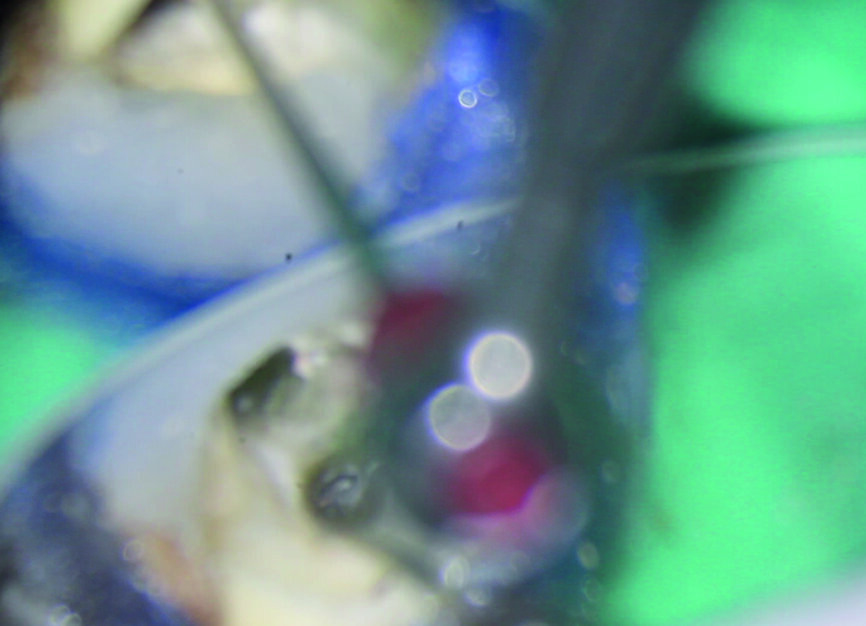

Une anesthésie locale est réalisée, la dent est isolée avec une digue et la cavité d’accès est préparée. L’obturation en gutta-percha située en coronaire du fragment est éliminée au moyen d’une pièce à main sonique (SONICflex 2003 L, KaVo) et de limes Micro Type D (MANI), sous examen microscopique direct (Fig. 2). Ensuite, une plate-forme de travail périphérique est préparée au niveau de l’extrémité coronaire du fragment. Pour ce faire, une fraise Gates–Glidden modifiée de taille 3 (MANI ; Fig. 3) est utilisée à basse vitesse de rotation de 300 trs/min et dirigée apicalement jusqu’à entrer en contact avec le fragment instrumental fracturé. La procédure est réalisée dans chaque canal (Figs. 4 et 5). La plate-forme doit être légèrement plus large que le diamètre coronaire du fragment (Fig. 6). Un espace est créé autour du fragment au moyen d’une pièce à main sonique (SONICflex Quick 2008 L, KaVo) munie d’un insert Endo Clean de taille 25 (portion coronaire exposée sur 2 mm). Au cours de cette étape, le même insert est utilisé pour émousser la partie active (lames) de l’instrument fracturé, afin d’éviter d’endommager la boucle du fil métallique (Figs. 7a et b) qui servira de lasso.

Figs. 7a et b : Création d’un espace autour du segment coronaire de l’instrument fracturé avec SONICflex Quick 2008 L muni d’un insert Endo Clean de taille 25.